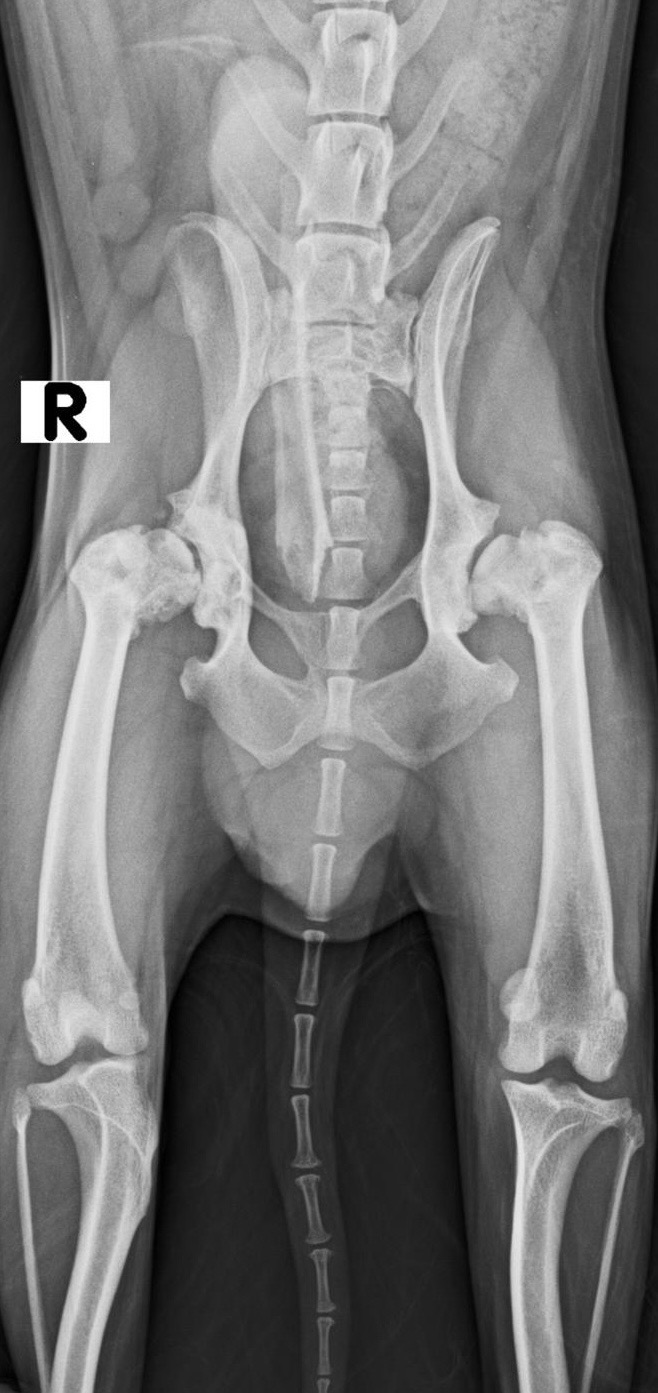

Traumatología y ortopedia

Radiología